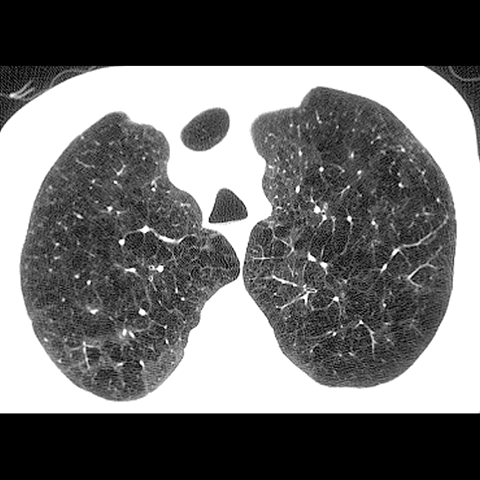

A 62 year-old male presents with chronic shortness of breath (Axial HRCT). [4 of 6]